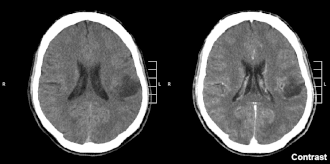

Glioom in linker pariëtale kwab (CT-hersenscan), tweede graad volgens WHO.